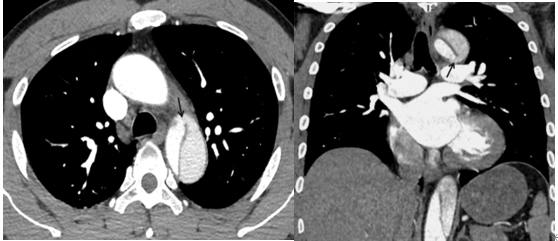

薄层横断面图像及多平面重组图像可以看到夹层破口(黑箭),表现为真腔和假腔之间沟通的通道。

真假腔的显示:真、假腔可同时显影,或假腔强化和排空比真腔延迟,一般情况假腔较大,真腔较小。(真腔黄箭,假腔白箭)